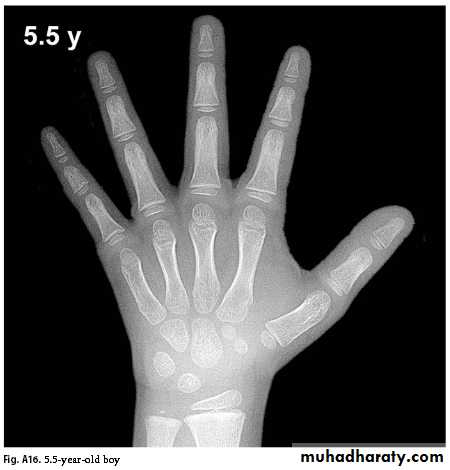

Bone Age

Greulich & Pyle: Radiographic Atlas of Skeletal Development of the Hand and Wrist, This method involves a complex comparison of all the bones in the hand and wrist against reference radiographs of different ages.

Delay of 2 years or more in bone age is significant.